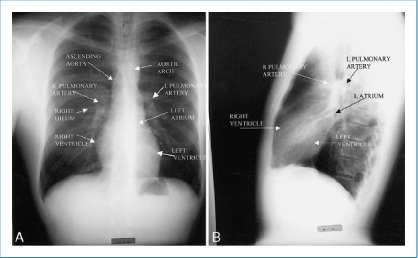

2. Identify the major cardiovascular structures that form the silhouette of the mediastinum. Right side: Ascending aorta, right pulmonary artery, right atrium, right ventricle

Left side: Aortic knob, left pulmonary artery, left atrial appendage, left ventricle